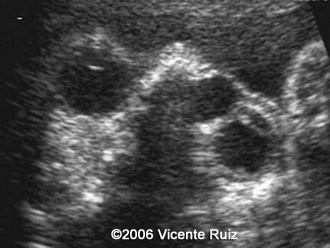

This is a case of dacryocystocele in a third  trimester fetus. Note the cystic mass between the right medial cantus and the nose.